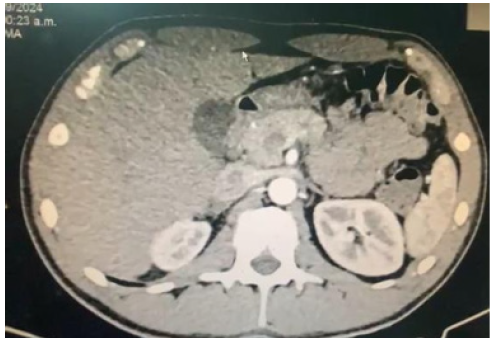

On the second day of hospitalization and the fifth day of illness, due to persistent abdominal pain without improvement, accompanied by a fever spike of 38.4°C and the presence of an epigastric mass on physical examination, a contrast-enhanced CT scan was ordered due to suspicion of local complications. Blood tests were repeated, including procalcitonin levels and blood cultures. In the meantime, the patient received only symptomatic treatment without antibiotics. Laboratory results returned with Hb 13.2g/dL, Hct 39%, WBC 17,270/mm³ with 82% segmented neutrophils, platelets 192,000/mm³. Creatinine was 0.7mg/dL, electrolytes were within normal limits. Liver function tests showed GOT 22U/L, GPT 11U/L, total bilirubin 0.77mg/dL with direct bilirubin 0.33mg/dL, amylase 509U/L, and lipase 312U/L. Procalcitonin was 0.3ng/mL, and no bacterial growth was observed in the blood culture. The contrast-enhanced abdominal and pelvic CT scan revealed a normal liver and gallbladder with no tomographically evident alterations. The pancreas was globally enlarged, with the head measuring 48mm in its craniocaudal diameter, and the margins were diffuse with peripancreatic fat stranding and adjacent fluid collections extending along the left paracolic gutter down to the pelvic cul-de-sac. There was homogeneous enhancement in the head and body of the pancreas, with decreased enhancement noted in the tail, suggesting a possible necrotic area involving less than 30% of the parenchyma. The main pancreatic duct was preserved caliber. These findings were consistent with acute pancreatitis with peripancreatic fluid collections, a tomographic severity index of 5 points, classified as moderate pancreatitis (Balthazar D), with probable necrosis involving less than 30% of the pancreas (Figure 2).

Figure 2: Contrast-Enhanced CT Abdomen. Peripancreatic fluid collections. Balthazar D, probable necrosis less than 30%.